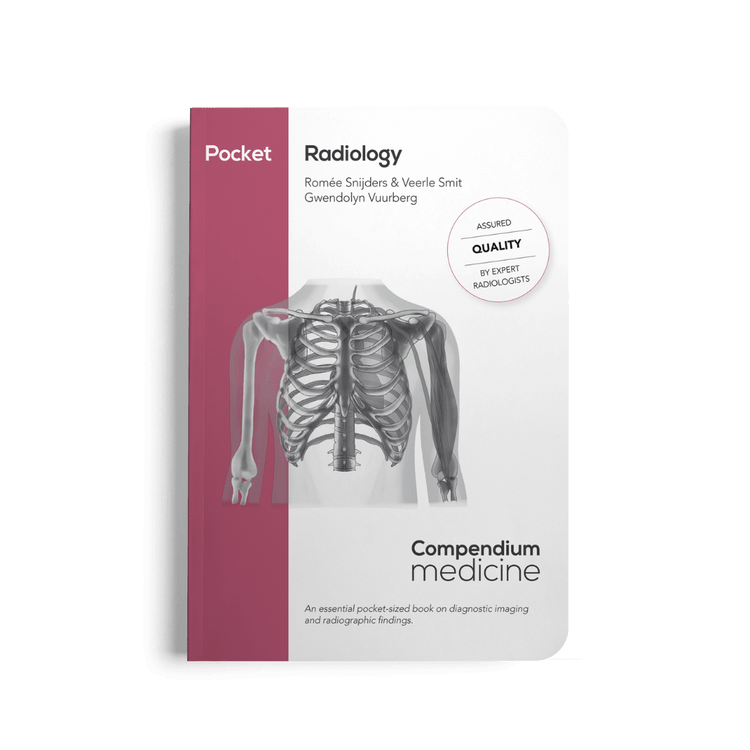

Pocket Radiology (2023)

Pocket Radiology (2023)

This compact handbook breaks down the essentials of radiology into clear, structured overviews – so you can scan, interpret, and act with confidence.

- Master key imaging modalities and findings – from X-rays to CT and MRI.

- Covers essential acute radiological and non-radiological conditions.

- Designed for fast reference: visual, concise, and easy to carry.

Product details

Product details

- Language: English

- Written and updated according to the latest guidelines

- ISBN: 978-90-831909-8-3

- Print length: 209 pages

- Edition: first (2023)

- Dimensions: 170 mm x 120 mm, the pocket fits in your white coat!

- With two flow diagrams on the diagnostic evaluation of dyspnoea and abdominal pain.